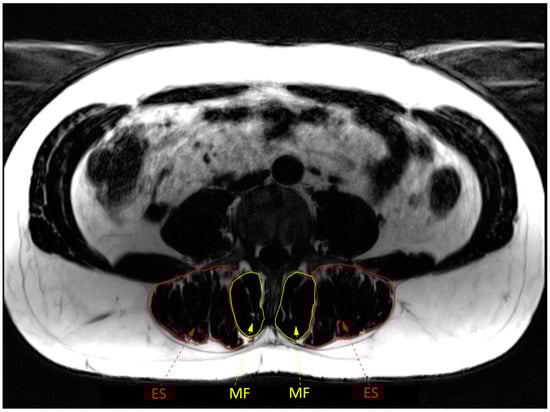

2.2. Muscle Structure